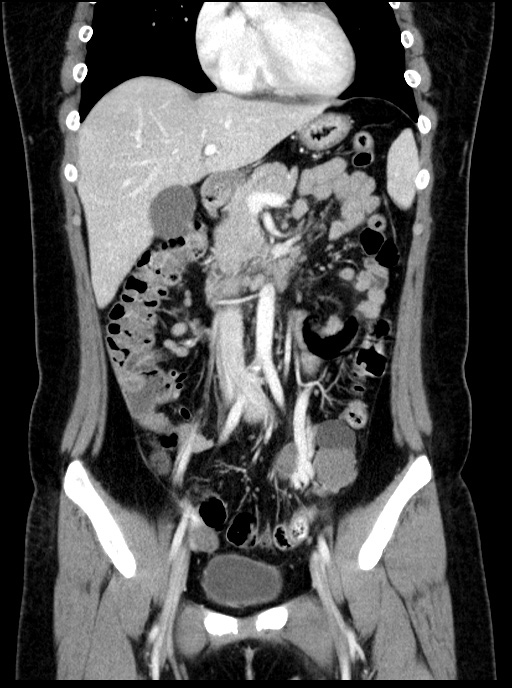

초음파영상에서 보였던 낭성병변은 CT에서는 하행결장과 뚜렷하게 떨어져 있었기에 duplication cyst는 배제할 수 있으며, lymphangitic cyst의 가능성도 떨어져 보입니다. 해당 병변은 Lt. adnexal region에 있는 병변으로 생각됩니다.

조영증강이 되지 않고, 초음파에서 무에코음영을 보인 부분은 단순낭종으로 생각할 수 있습니다. 초음파영상에서 약간의 에코음영이 보였던 부위는 조영증강이 되지 않은 대신 균일한 연부조직음영을 보여 낭종 내에 출혈 가능성을 배제하기 어려웠습니다.

관상면 영상에서 해당 병변은 확실히 Lt. adnexal region의 병변입니다. 여기에 더해 좌측 tube가 함께 두꺼워져 있습니다. 이렇게 tubal thickening이 있으면서 주변에 염증반응이나 조영증강소견이 동반되지 않는 경우는 ovary torsion의 가능성을 배제할 수 없습니다.